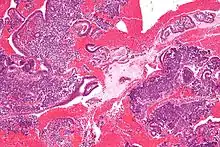

Endometrioid adenocarcinoma from biopsy. H&E stain.

Micrograph of decidualized endometrium due to exogenous progesterone. H&E stain.

Micrograph showing endometrial stromal condensation, a finding seen in menses.